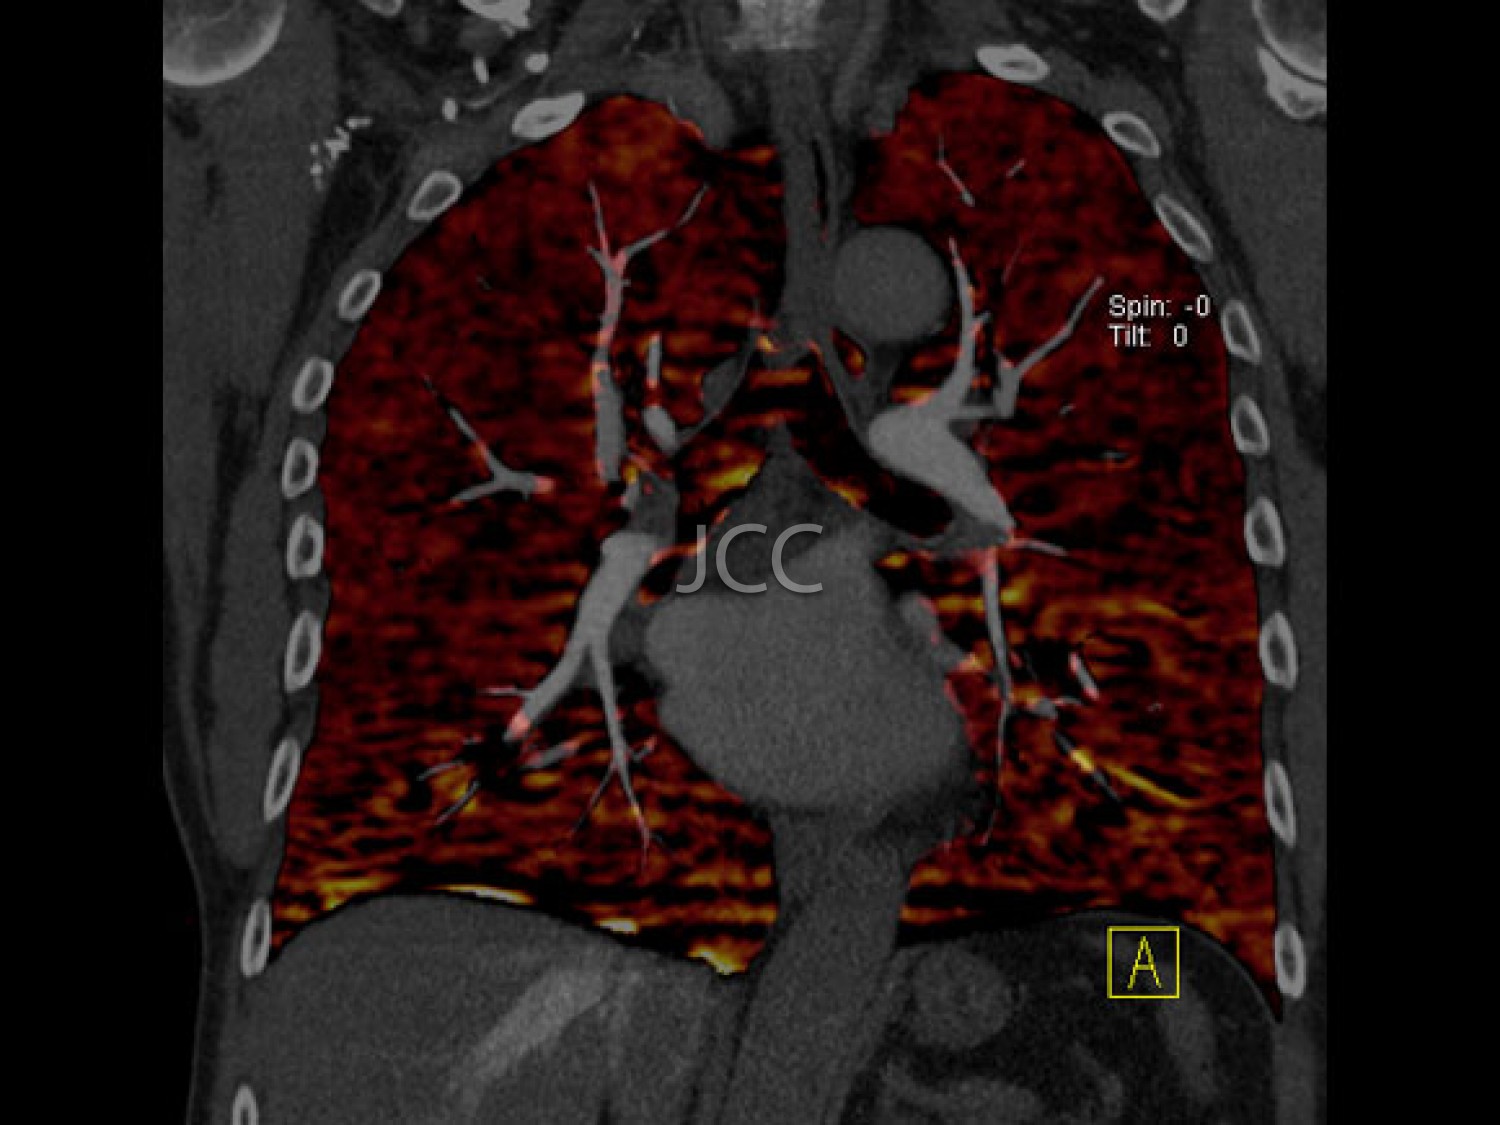

A introdução dos mais recentes sistemas de tomografia computorizada Dual-Source, primeiros equipamentos destes instalados em Portugal – Siemens Somaton Definition FLASH e DRIVE, com dupla ampola e duplo detector, permite a aquisição de 256 imagens em 0.28 segundos, utilizando-se uma dose de radiação muito reduzida, bastante inferior à utilizada, nomeadamente nos equipamentos de 64 cortes, geralmente utilizados para avaliação cardíaca, nomeadamente das artérias coronárias. Associamos ao nosso programa de rastreio a última tecnologia em ressonância magnética 3 tesla para despiste de patologias cerebral, prostática e mamária.

IMAGEM PREVENTIVA

Pela 1ª vez na história da medicina, através da tecnologia multi-detector, com dupla ampola e ressonância magnética de última geração 3 tesla, é possível, de modo não invasivo e capacidade diagnóstica comprovada, efectuar o screening de processos patológicos, para prevenção de doença cardíaca, neoplasias e acidente vascular cerebral – AVC. Salienta-se que com o nosso equipamento de TAC dual source - 256 cortes -  a dose de radiação é  muito baixa (cerca de 10 vezes inferior à dose dos equipamenos de TAC de 64 cortes).  Os dados obtidos nestes equipamentos de ultima geração são tratados em estações de trabalho de alto nível, que utilizando sistemas CAD e de visualização tridimensional, resulta em informação detalhada e muito rigorosa.

O conjunto destes exames com este tipo de equipamento constitui a modalidade de escolha para o estudo imagiológico do corpo humano, através de angiografia não invasiva do coração, do cérebro e dos vasos do pescoço, colonoscopia virtual por TAC assim como a avaliação dos restantes orgãos e estruturas ósseas do tórax, do abdomen e da pélvis, o estudo da próstata no caso do homem e da mama no caso da mulher.

CHECK-UP CARDIO-TORÁCICO

• Angio TC das Coronárias

• TC do Tórax